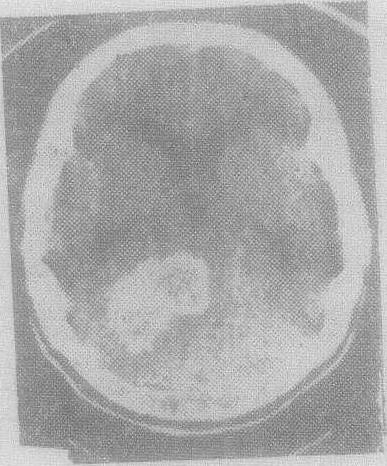

颅内各种正常组织的吸收系数各不相同,脑脊液最低,约在+2~+12Hu单位,脑白质约在+25~+34Hu单位,脑灰质30~40Hu,松果腺和脉络丛则更高。因此在图象上可显示出脑室、脑池和脑实质的形态和位置(图1)。

图1 CT扫描显示脑和脑室的正常形态